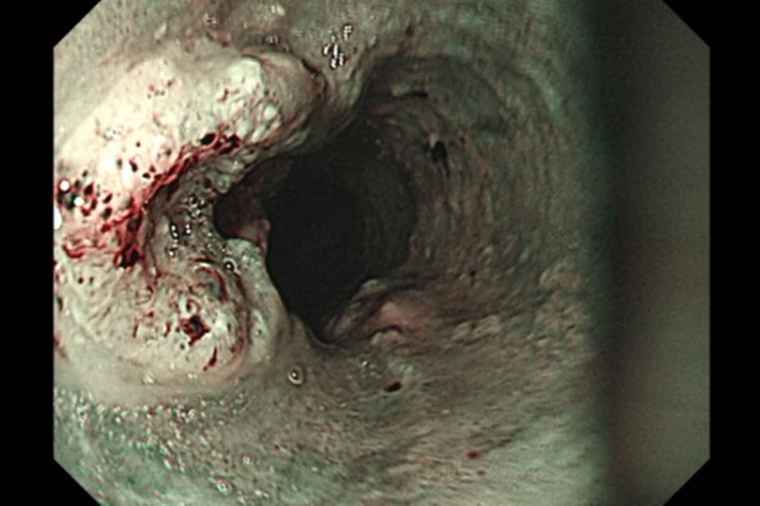

胃鏡檢查是診斷食道癌最常使用的方法,可直接觀察腫瘤並進行切片確認,同時搭配電腦斷層、全身骨掃描、腦部磁振造影、全身正子攝影等評估轉移情形。洪嘉聰表示,食道癌治療會依期別與病灶範圍調整,但手術切除仍是首要考量。傳統開胸手術需於胸腹切開約15~20公分大的傷口,且易併發肺炎;若合併下咽癌,可能得進一步施行全喉切除與永久氣切,造成語音、進食與呼吸功能的永久改變。現今微創技術則可透過胸腔鏡與腹腔鏡完成,過程只需在胸腹部開數個1~2公分的小切口,並於頸部開4~5公分的切口進行胃管上拉及頸部食道縫合重建,術後恢復較快,併發症風險也相對降低。

# 首圖來源/台北慈濟醫院提供